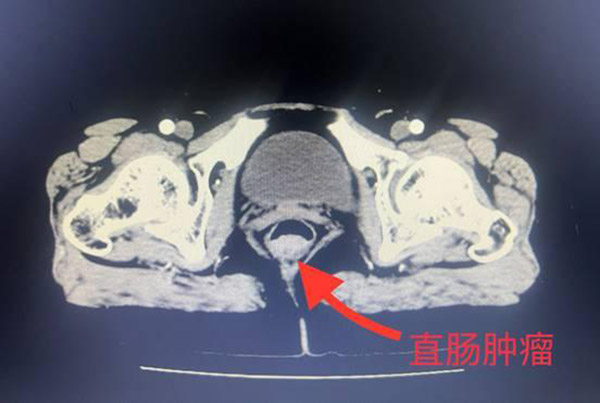

一段时间以来,李女士饱受便血的困扰,起初按照痔疮对症治疗后并无缓解。听从医生的建议,李女士在市六院办理了住院,经过进一步的肠镜检查,她被诊断为直肠癌。

肿物紧邻肛门,手术治疗又要保住肛门,避免李女士成为“造口人”,这成了一个现实的问题。面对忧心忡忡的李女士,王主任结合病情,向她推荐了腹腔镜下直肠癌ISR术。